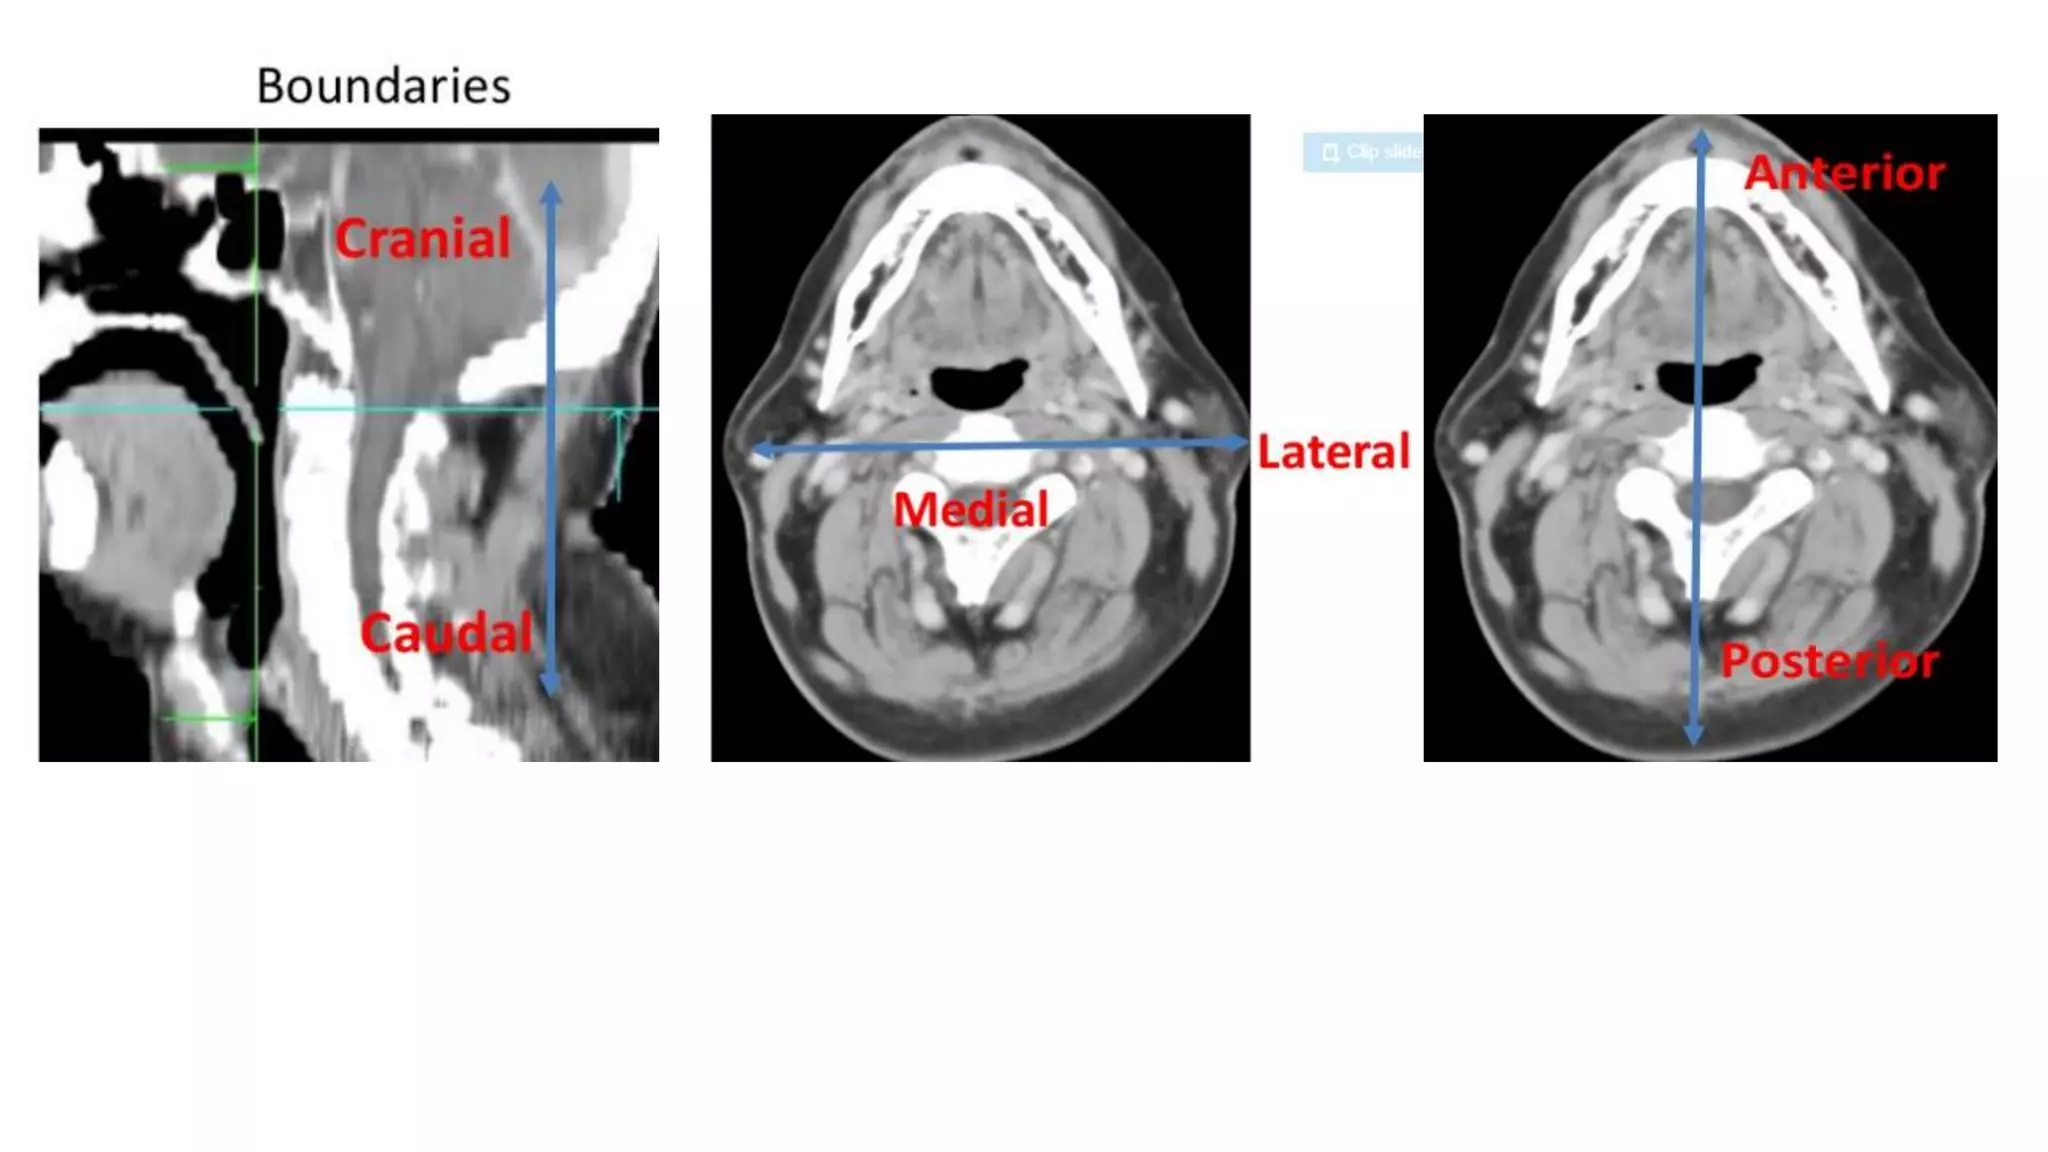

Axial CECT Neck

At Level Of C4